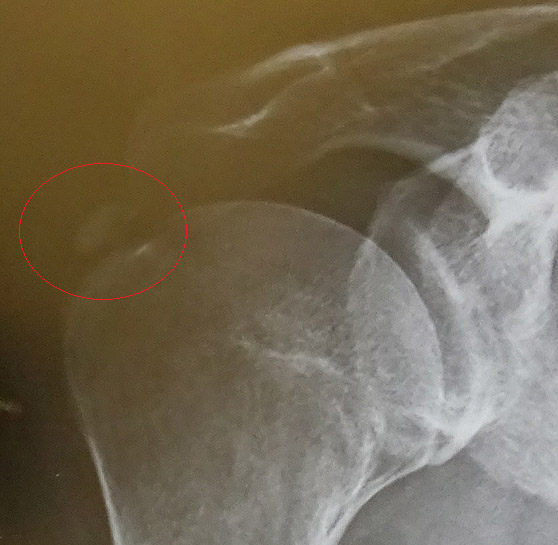

病名は、「石灰沈着性腱炎」

昨日、大きい病院に予約を入れ、本日治療して来ました。

火曜日にこれも別の医者ですがステロイドを注射して、注射針で石灰を砕く事をやってもらっていたので、今日は太い注射針にて液をの注入と吸引を繰り返して、柔らかくなった石灰を抜いてもらいました。

固いと抜き切れないらしいですが、今日の医者は抜けたんじゃないか?と満足そう。

右肩の動きが良くなってきたような・・・(喜)

月曜日の治療前の物。

それと、肺に影があるのは肺繊維症、通称 塵肺の名残なので御心配なく!(笑)

拡大画像を自分の物